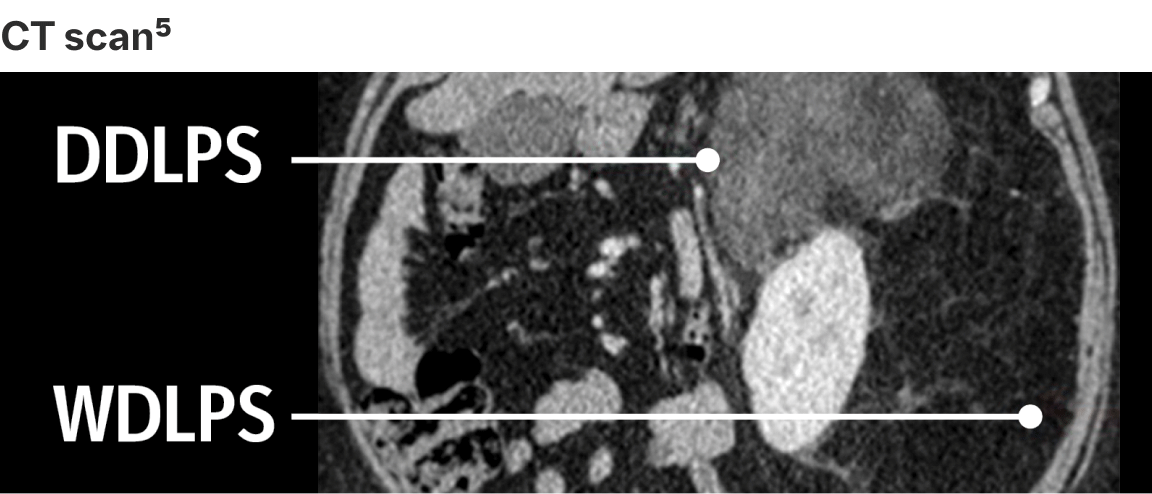

To complement the histological analysis, cross-sectional imaging based on tumour location assists in the establishment of differential diagnosis6

DDLPS CT scan

J Clin Oncol 36:151-159. © 2017 by American Society of Clinical Oncology. Licensed under the Creative Commons Attribution 4.0 License: http://creativecommons.org/licenses/by/4.0/